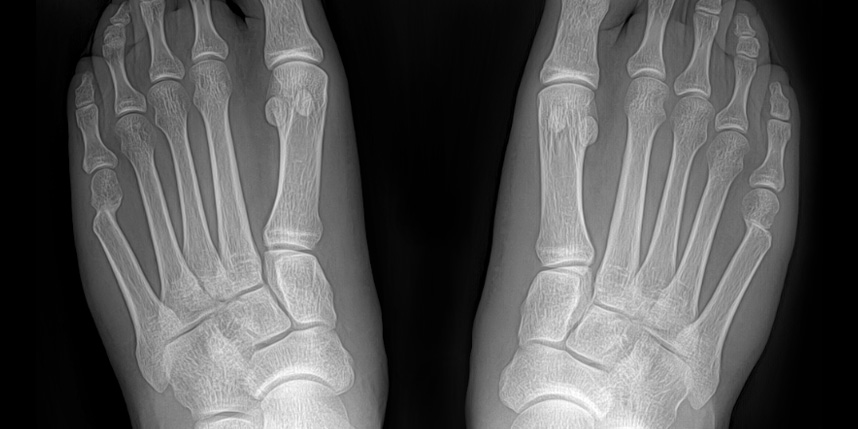

새끼발가락 관절의 통증

신발을 신었을 때 통증이 심해지며, 걷거나 서 있을 때 불편함을 느낌

튀어나온 부분에 염증이 생기거나 굳은살이 박힘

심한 경우 새끼발가락이 다른 발가락 쪽으로 휘어지거나 겹칠 수 있음